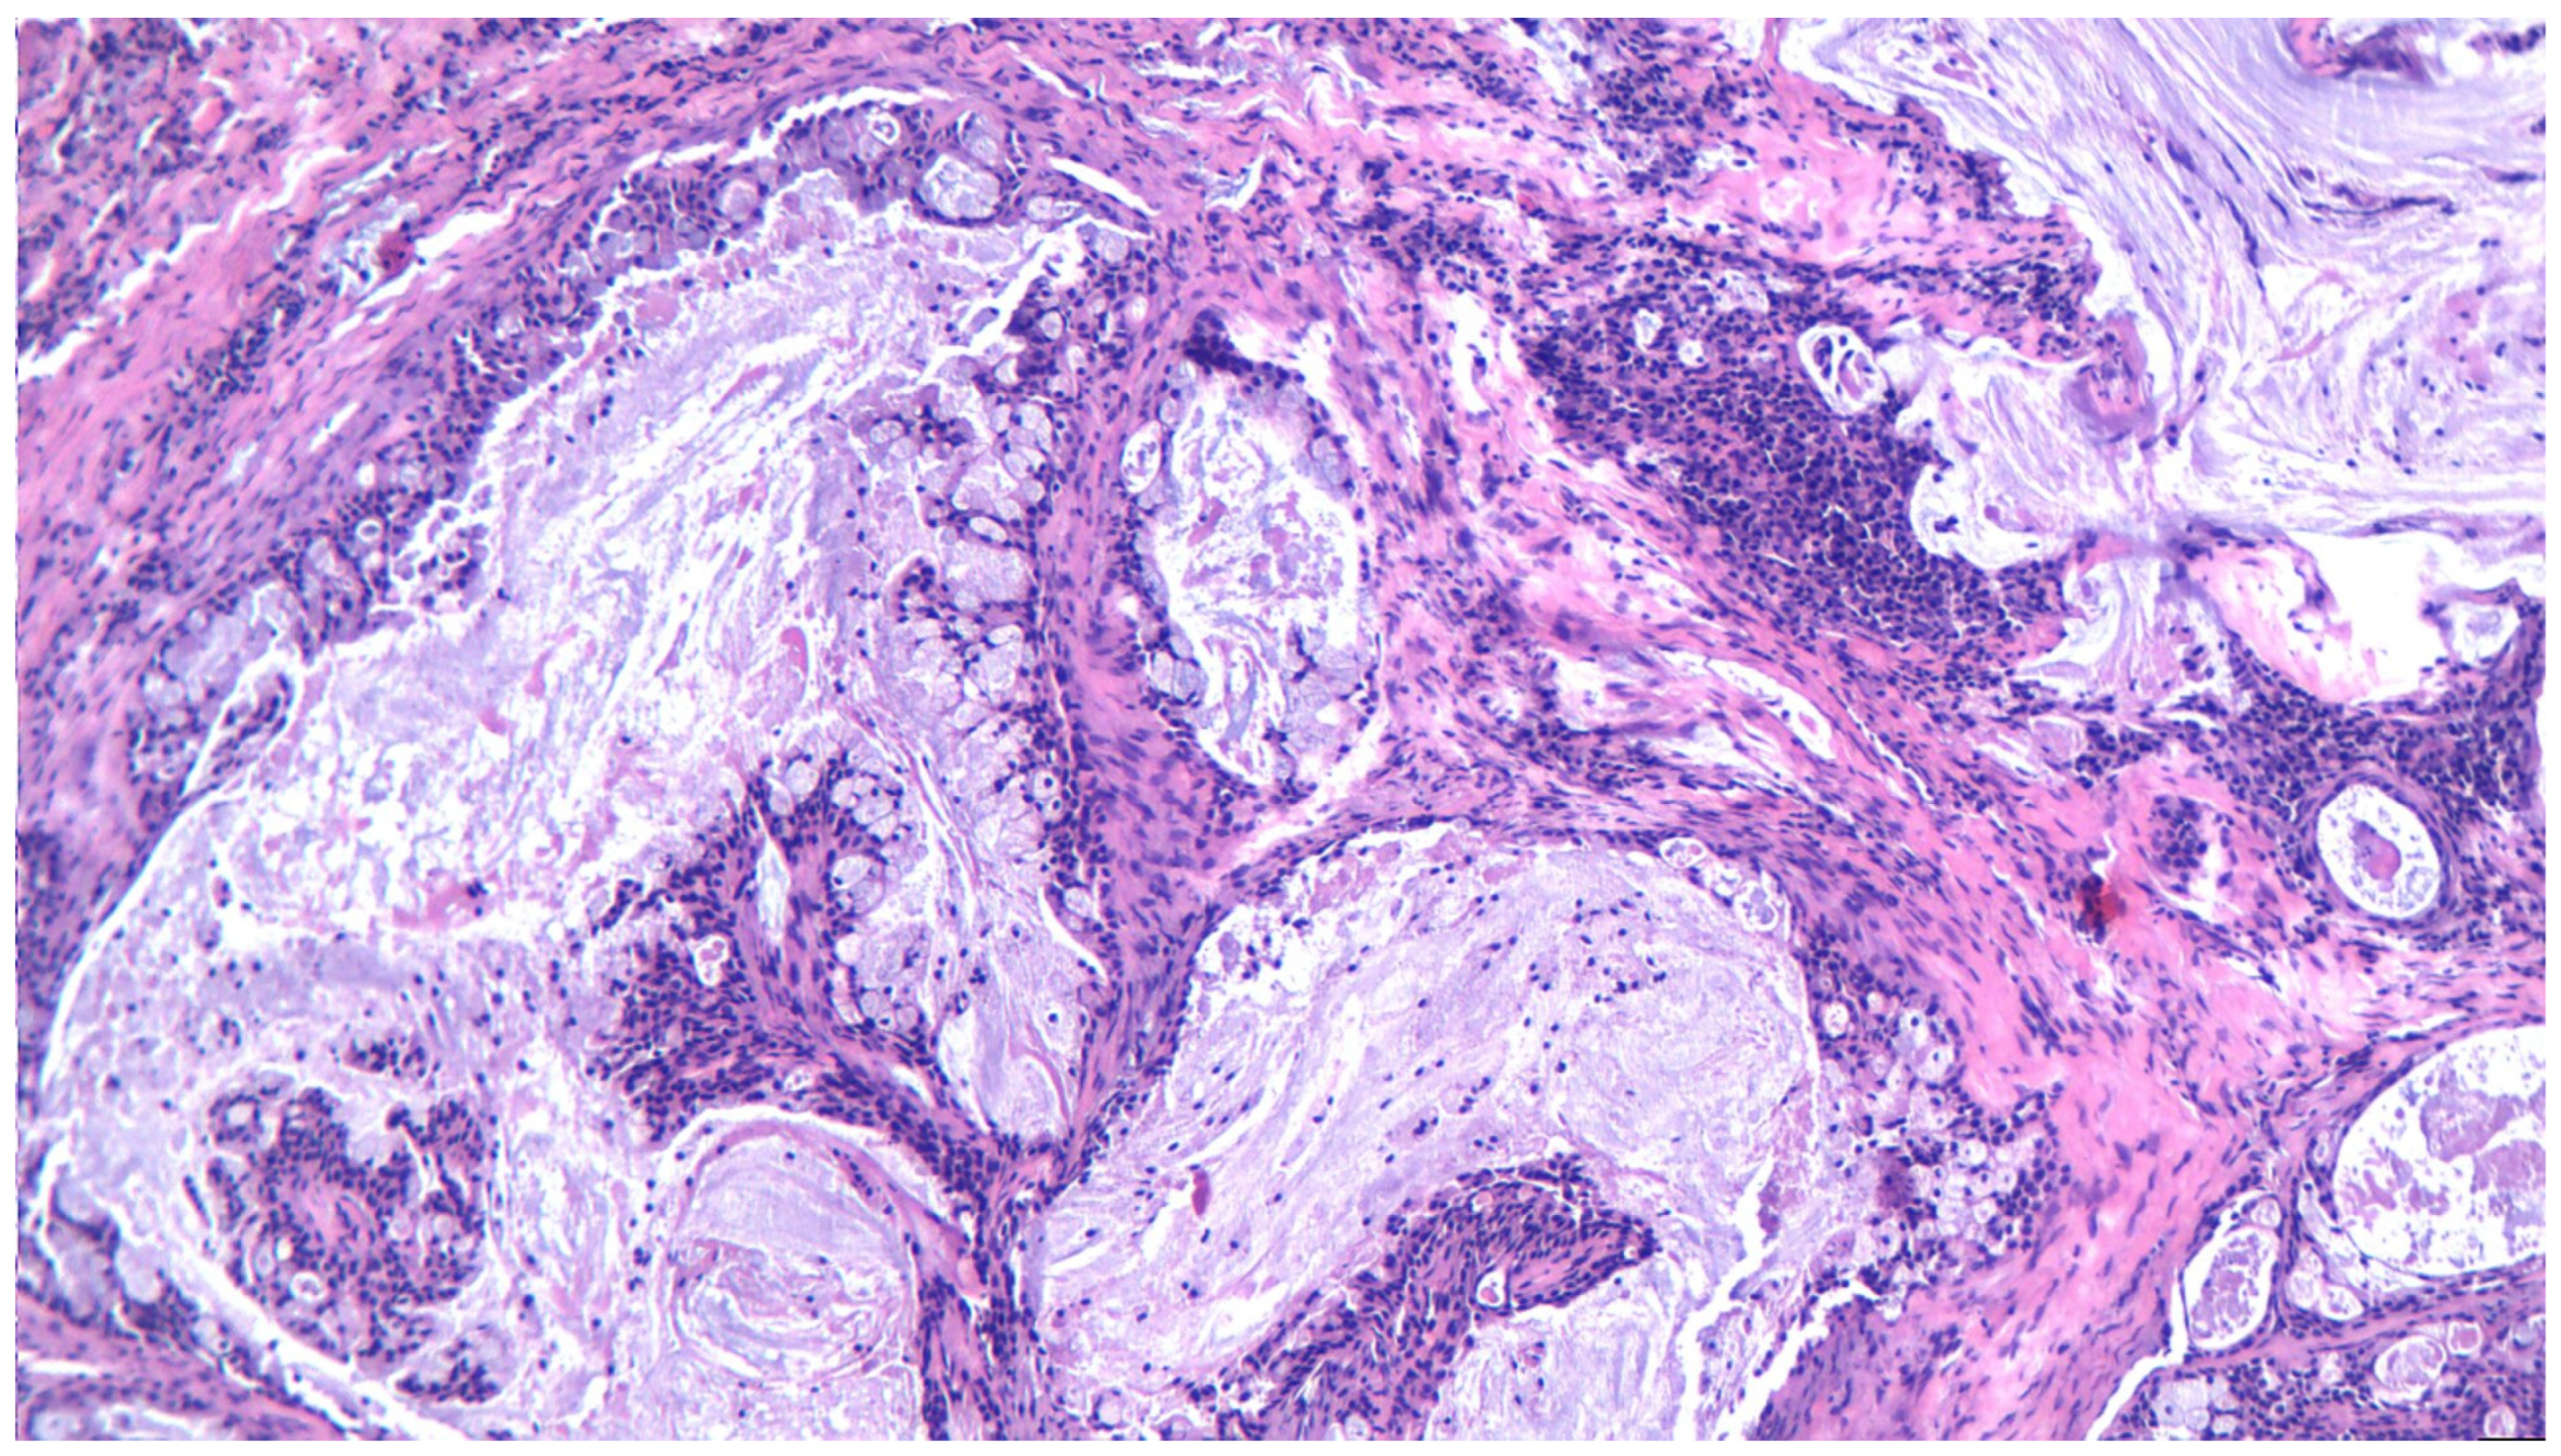

3.10. Adenocarcinoma